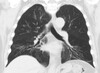

What pathology is seen here?

Interstitial Pneumonia

52